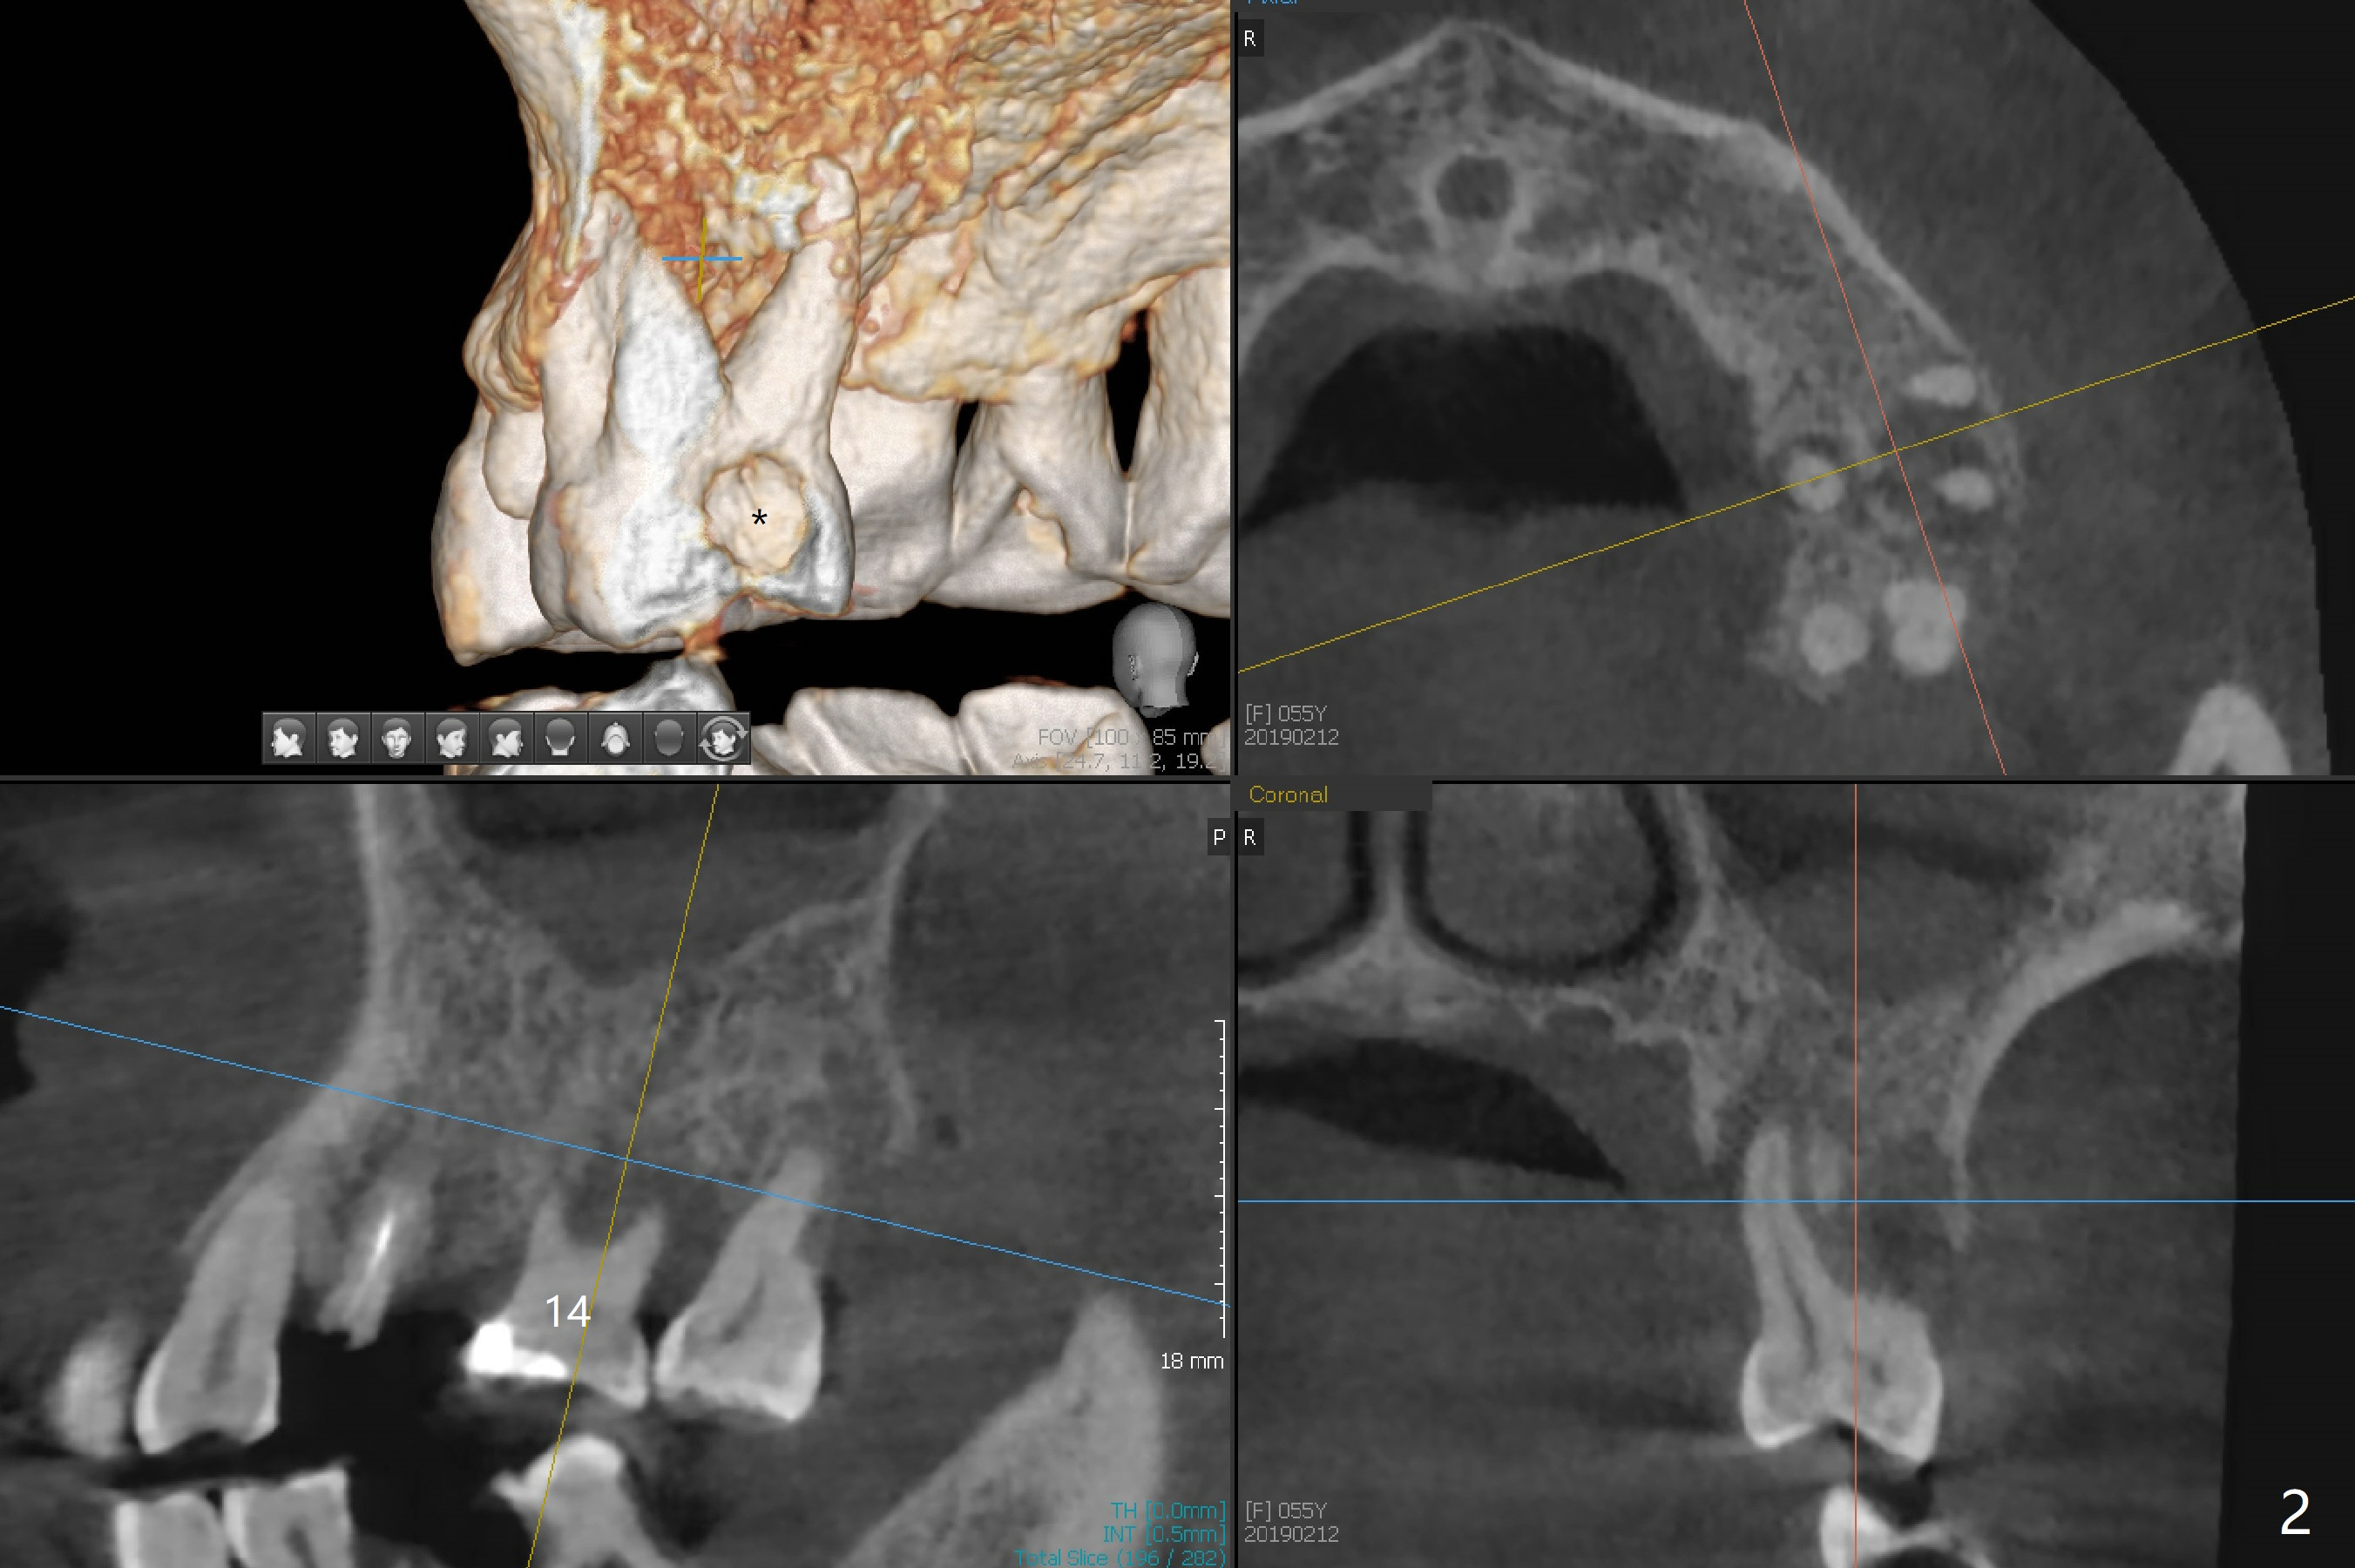

A 55-year-old woman has poor dentition, which is partially related to her previous history of ice chewing (Fig.1). The long bone height in the jaws suggests bruxism and requires as many teeth and implants as possible. After SRP, caries will be removed from #14 and 15 for determination of salvageability (Fig.2). The patient prefers to save the tooth #30. Endo referral will be recommended for #14 and 30. If the tooth #14 proves to be nonsalavageable, it will be extracted with #12 for immediate implants and subsequent FPD (Fig.3,4). Immediate implant will be avoided at #19 due to severe bone loss. Instead a short implant (5.5x5 or 6 mm) will be placed at #18, while a 4x11.5 mm one at #20 for FPD (Fig.5,6). All of the implant will use guides. There is a special point at #18. After use of 4.5 mm drill, the guide will be removed for free hand osteotomy using 5.0 mm drill, 5.5 mm tap and implant placement. PRF will be prepared for membrane and sticky bone at #19 and 20. For the lower right quadrant, treatment for #30 should be conducted first, either RCT or implant. The tooth #29 will be uprighted using #30 as an anchor, if the former is salvageable. The implant at #28 will be placed last (Fig.7,8).